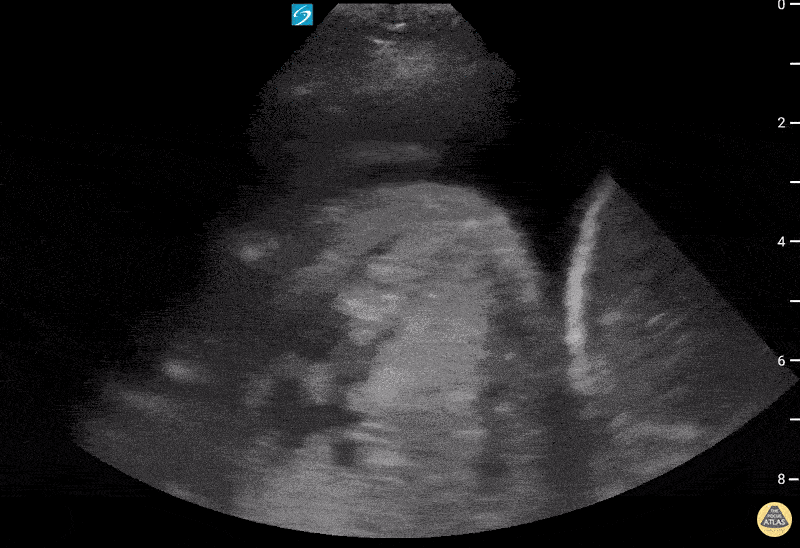

Pulmonary - Large pleural effusion with hiatal hernia

72 year old with past medical history of hiatal hernia presenting to the ED with new onset shortness of breath requiring rescue BPAP. She was diagnosed and treated with CHF exacerbation. Lung ultrasound showed a large pleural effusion with uncertain mass-like object with heterogenous fluid contents on the right (shown here), along with dense B-lines. Correlation with prior CT suggested that the structure on the right chest was a large hiatal hernia. Contributed by: William McGill, PA-C